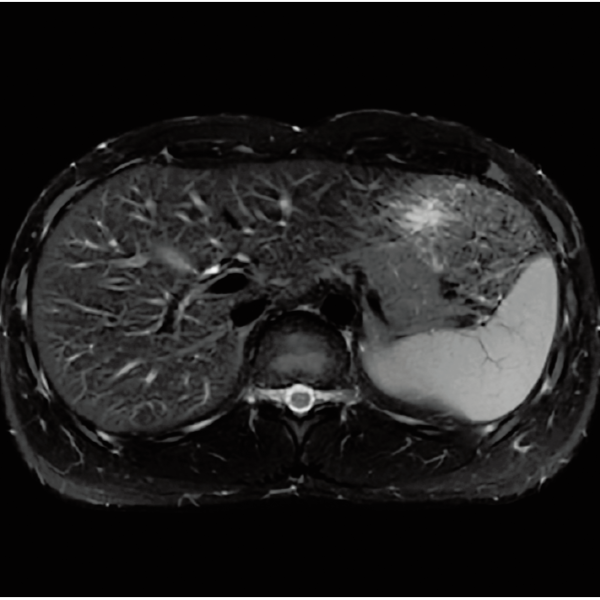

T1WI Dual Echo (Out) 息止め

T2*WI RADAR, 2:34

T2WI FatSat 呼吸同期併用RADAR, 2:16